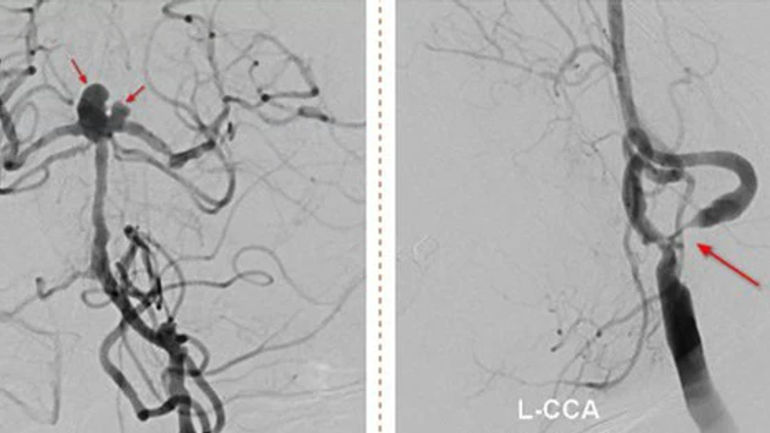

Ngày 4/3, Bệnh viện Đa khoa S.I.S Cần Thơ tiếp nhận bệnh nhân C.T.M (nữ, 71 tuổi) với tình trạng liệt nửa người, mặt lệch, mặt méo. Ban đầu, chẩn đoán bệnh nhân bị nhồi máu não bán cầu trái. Tuy nhiên, sau khi chụp MRI, phát hiện thêm nguy cơ vỡ túi phình, đe dọa đến tính mạng bất cứ lúc nào.

BS Nguyễn Đào Nhật Huy cho biết bệnh nhân có nhiều vấn đề sức khỏe khác như hẹp mạch máu, tăng huyết áp, thiếu máu và bệnh thận mạn giai đoạn 3. Sau hội chẩn, quyết định đặt stent kết hợp thả coil để cứu nguy cho bệnh nhân. Tuy nhiên, do nguy cơ vỡ túi phình cao, việc can thiệp không dễ dàng.